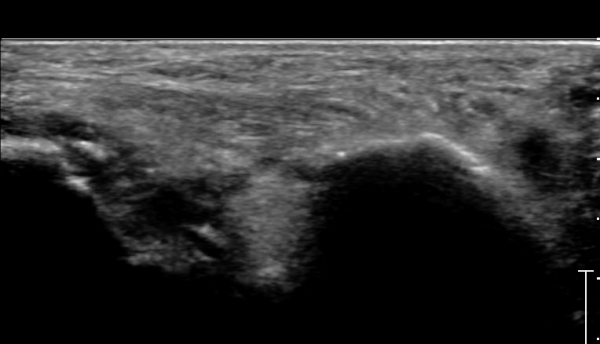

Á¾°ñÀÔ¹æ°ñ°üÀý Á¾´Ü¸é°Ë»ç»ó Á¾°ñ Àü¹æµ¹±â °ß¿­°ñÀý°ú Á¦4ÁßÁ·°ñ °ß¿­°ñÀýÀÌ °üÂûµÈ´Ù(»çÁø 2).